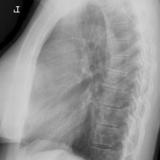

Case 9 Thymoma Lat

Date: 04/04/2010

Views: 3182